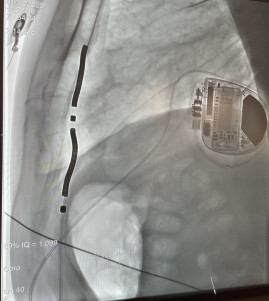

Oggi il team di Elettrofisiologia ha impiantato con successo i primi due defibrillatori Extravascular AURORA™ (Medtronic).

Questo dispositivo innovativo utilizza un elettrocatetere di shock intramediastinico, che consente di erogare terapia di defibrillazione senza accesso transvenoso, riducendo i rischi legati ai sistemi tradizionali.

A differenza dei defibrillatori sottocutanei, l’AURORA™ ICD offre anche antitachycardia pacing (ATP) e pacing bradicardico, combinando i vantaggi di un approccio completamente extravascolare con la versatilità terapeutica dei sistemi convenzionali.